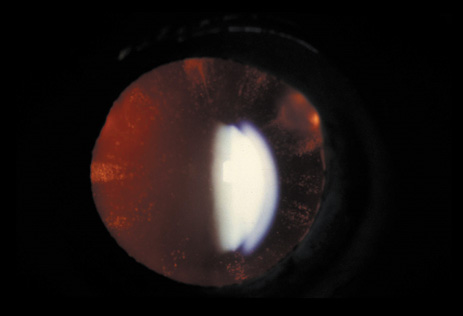

Sunflower cataract is named after the patel-shaped alignment of tiny anterior subcapsular copper deposits. It is a rare manifestation of Wilson's disease (Fig. 5) and is present in 20% to 30% of patients with ocular manifestations. The copper-red to blue-green deposits form a disk-shaped central opacity in the anterior lens capsule, which is usually denser in the pupillary opening, with spoke-like radiations toward the periphery. Posterior lens capsule deposits appear in a fern-like pattern.19 The lens opacities may reverse on a low copper diet and treatment with systemic D-penicillamine.20

Fig. 5. Sunflower cataract. Copper-red to blue-green deposits in the area of the pupil form a disk-shaped central opacity with patel-shaped spoke-like radiations toward the periphery in a patient with Wilson's disease.